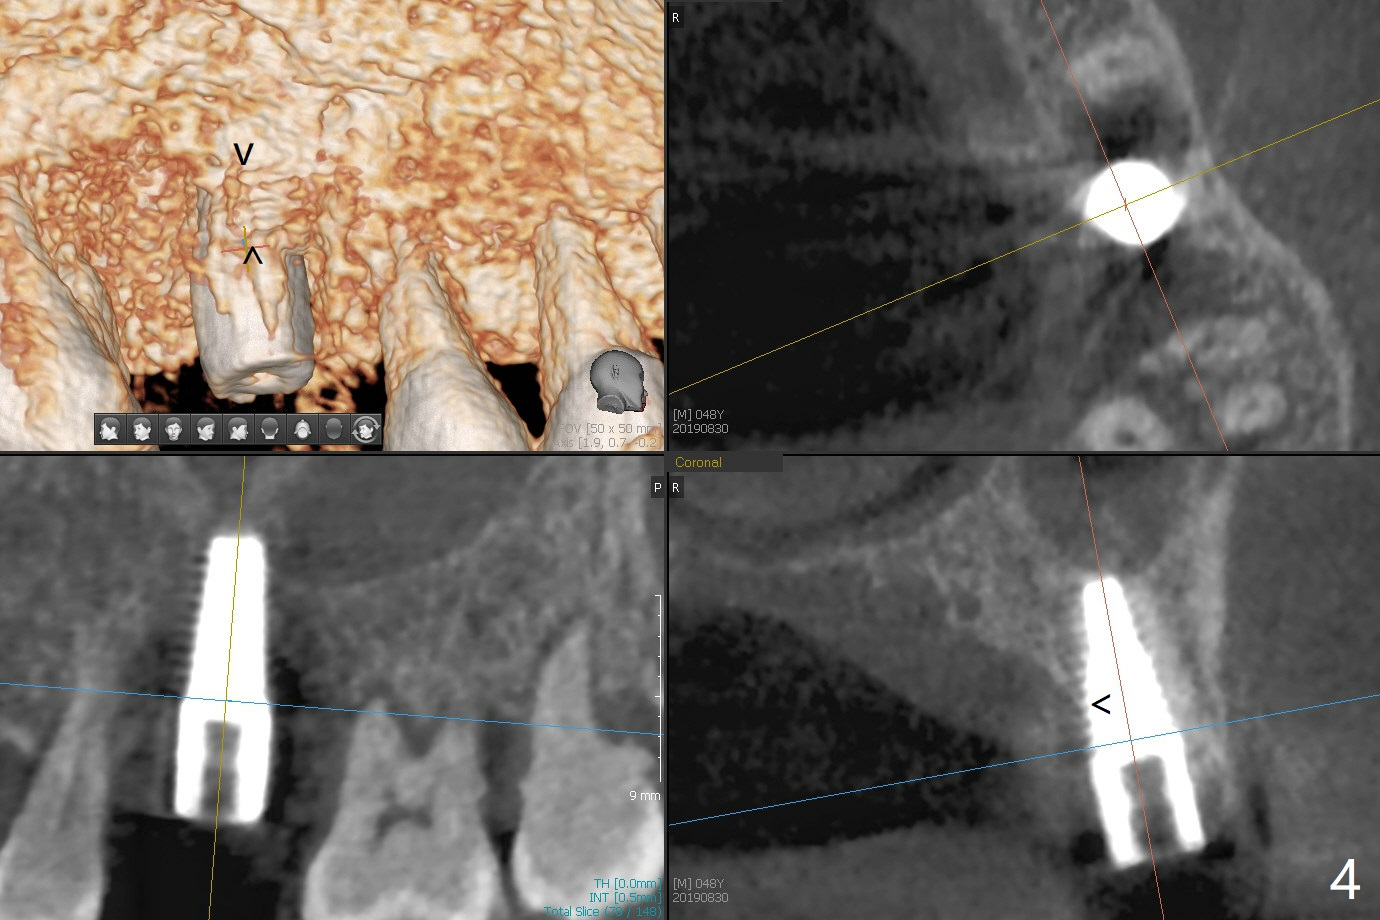

Immediately preop reanalysis of CT shows that there may be palatal thread exposure at #14 when a 4.5x14 mm tissue-level implant is placed equigingival (Fig.1,2). After sinus lift with IS 4x10 mm dummy implant with guide, the tissue-level tap and implant placed free hand look deep (Fig.3,3'). CT reveals possible 3 palatal threads exposed (Fig.4,5 arrowheads), which is associated with change in trajectory due to the palatal shift of the apex of the implant (arrow), as compared to the design of the bone-level implant (Fig.6). When there is a slope in the ridge and/or sinus floor, do not shift implants and use the guide for implant placement. If switching is necessary, use a final drill without underprep (Fig.7 red) through the sinus floor after sinus lift to avoid apical implant deviation. To fix the palatal thread exposure, palatal flap is raised. In fact the implant has to be removed for the incision. When the implant is re-placed deeper by ~ 1mm, there is a thread exposed. Bone graft is placed with collagen membrane. As a 4.5x3 mm abutment is placed, the implant is found to be unstable. Periodontal dressing is applied. In fact the implant exfoliates with the abutment 4.5 months postop (Fig.8). Bone graft seems to be necessary (sticky bone). Tissue level implant should be avoided for patient with poor oral hygiene. Return to Upper Molar Immediate Implant, Trajectory II 3 Xin Wei, DDS, PhD, MS 1st edition 08/30/2019, last revision 05/18/2020